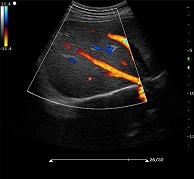

? ? ? ?C7為深圳安盛生物醫(yī)療技術(shù)有限公司新一代便攜式彩超產(chǎn)品,采用了先進(jìn)的PC平臺(tái),擁有強(qiáng)大的處理能力,優(yōu)異的圖像性能,集小巧輕便、全面的功能與輕巧流暢、特有的U型設(shè)計(jì)與一身,提供大眾新選擇。

? ?● 多種成像模式

? ? ? ?B、C、PW、CW、BCD三功、大角度偏轉(zhuǎn)成像、實(shí)時(shí)寬景成像、梯形成像(僅支持線(xiàn)陣)、解剖M型、彩色M型成像、組織多普勒成像、3D/4D成像

? ?● 彩色多普勒增強(qiáng)技術(shù)

? ? ? ?有效抑制彩色血流閃動(dòng)噪聲,提高血流分辨率和靈敏度